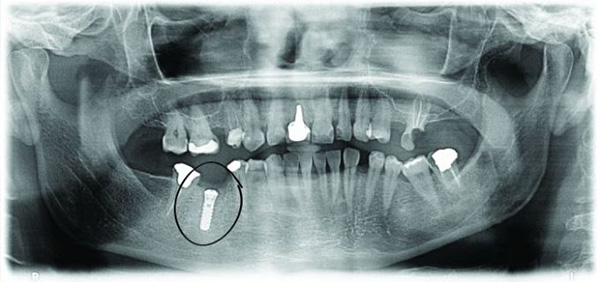

The first OTP image shows the remains of the tooth in position 46, infected and with broken roots. The only solution is extraction. If we were to proceed with the traditional method of root extraction, we would need to wait for 3 months before the wound was healed and we could place an implant. After the placement of the implant would have to wait for another 3 months before we could place the rest of the tooth on the implant. photo No.1.